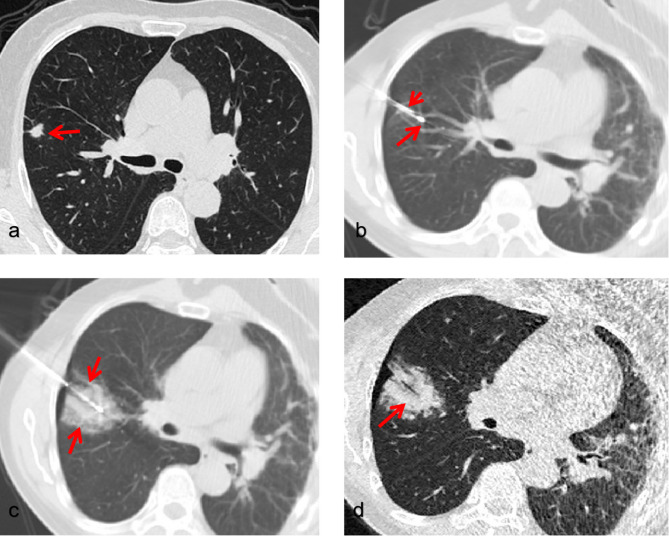

Methods: This retrospective study involved 124 patients with 131 highly suspicious malignant pulmonary nodules. Patients either underwent synchronous percutaneous core-needle biopsy and cryoablation (Group A) or separately underwent these procedures (Group B) from December 2020 to May 2024. All procedures were performed under CT guidance using a percutaneous approach. We analyzed technical success rates, complications, diagnostic yield, and local tumor control.

Results: Technical success rates were 100% in both groups. The rate of pneumothorax was 42.1% (16/38) in Group A and 34.9% (30/86) in Group B. In Group A, hemoptysis and pleural effusion rates were 18.4% (7/38) and 23.7% (9/38), respectively, while in Group B, these rates were 16.3% (14/86) and 12.8% (11/86). These differences were not statistically significant. The diagnostic positive rate in Group A was 87.5%. The mean follow-up duration was 11.8 months (95% confidence interval [CI], 10.2-13.4), with local tumor control rates of 97% for Group A and 88% for Group B. The effectiveness rates of synchronous and separate procedures were similar.